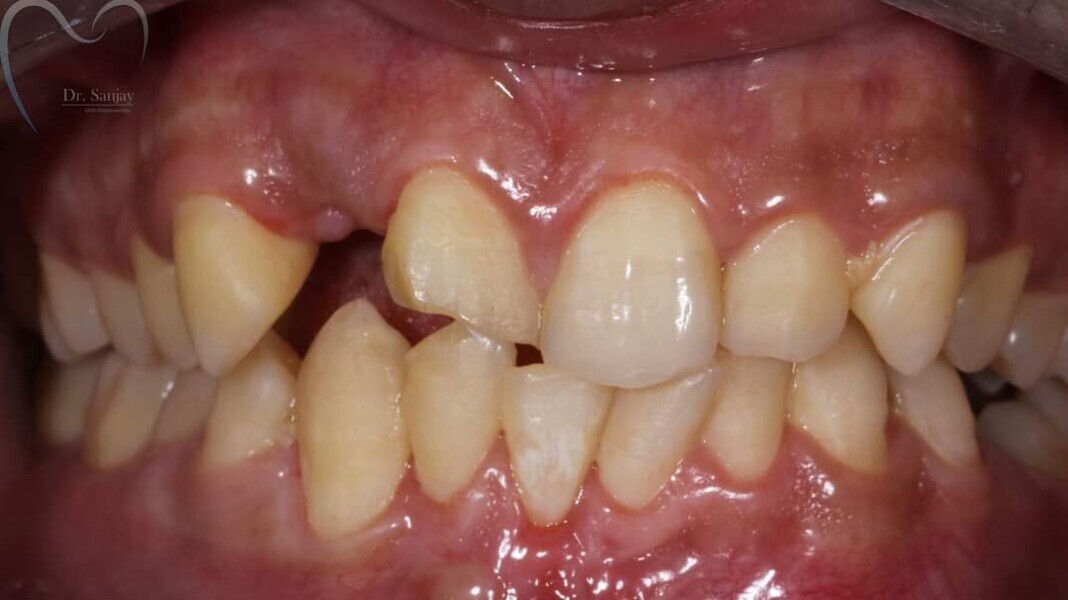

Esthetic Rehabilitation of Maxillary Anterior Teeth: Dr Sanjay Sah